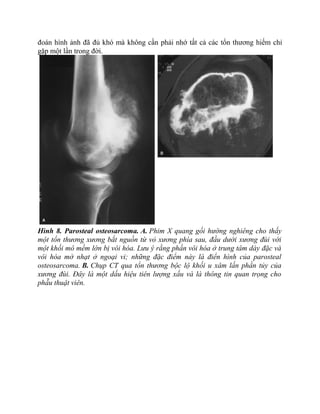

Hình 8. Parosteal osteosarcoma. A. Phim X quang gối hướng nghiêng cho thấy

một tổn thương xương bắt nguồn từ vỏ xương phía sau, đầu dưới xương đùi với

một khối mô mềm lớn bị vôi hóa. Lưu ý rằng phần vôi hóa ở trung tâm dày đặc và

vôi hóa mờ nhạt ở ngoại vi; những đặc điểm này là điển hình của parosteal

osteosarcoma. B. Chụp CT qua tổn thương bộc lộ khối u xâm lấn phần tủy của

xương đùi. Đây là một dấu hiệu tiên lượng xấu và là thông tin quan trọng cho

phẫu thuật viên.